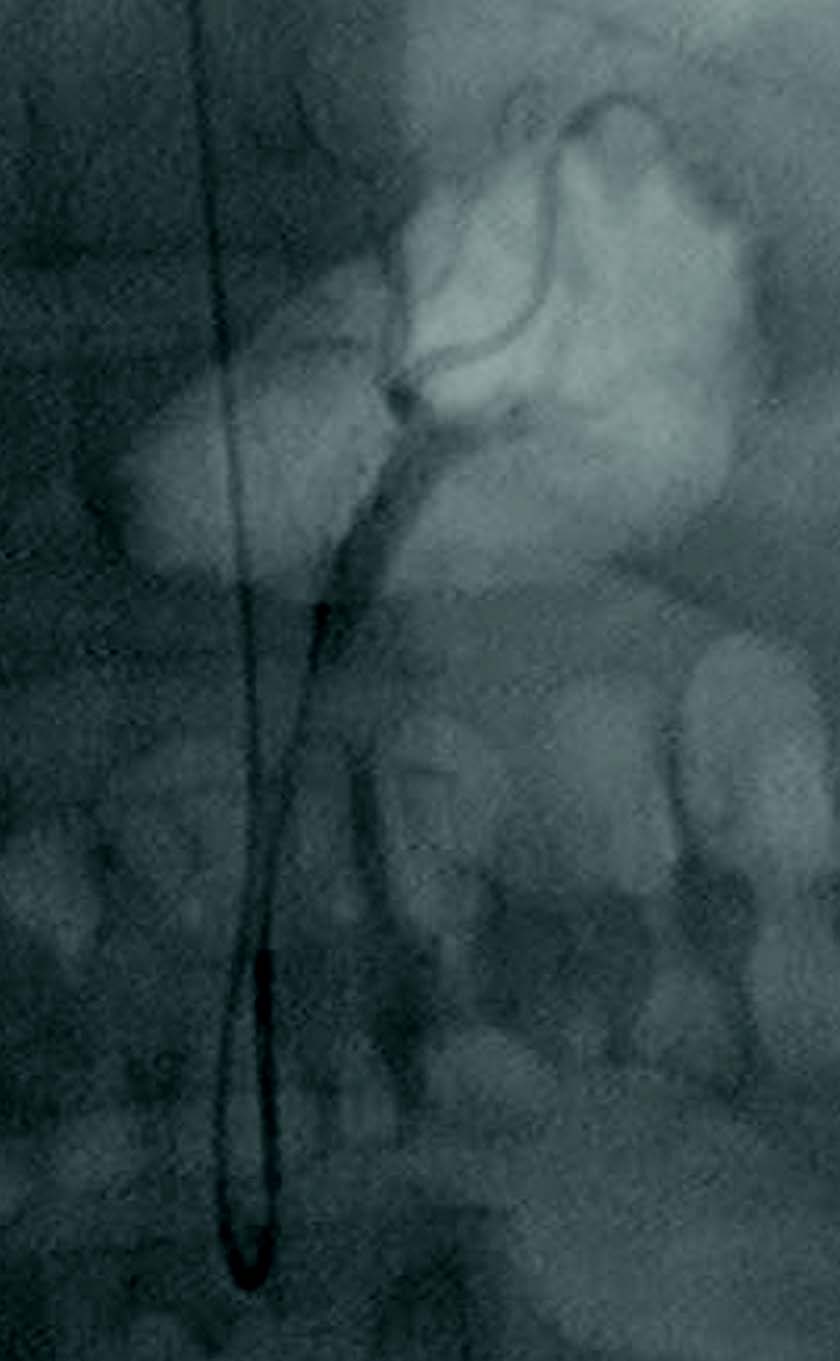

Embolization of the left gastric artery via radial artery approach in a morbidly obese patient.

As opposed to surgically removing part of the stomach, the embolization technique only requires access via the radial artery. “That's a very safe access site even in a very obese patient,” he said. Dr. Syed said he accessed the left gastric artery through the arm instead of the groin because the patients' fatty tissue makes those arteries difficult to locate in the first place and to later put pressure on to stop any bleeding.

The embolization technique suppresses the production of ghrelin, a hormone that stimulates appetite, by limiting blood flow to the area. This technique is less invasive and less traumatic than laparoscopic sleeve gastrectomy, Dr. Syed said.